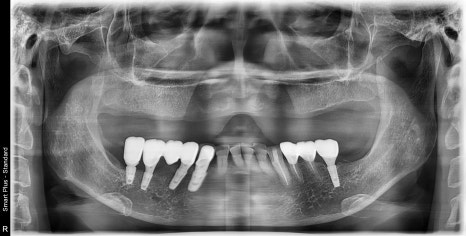

그러고 CT를 찍어보면

예전에는 그럴만도 했겠네요~

발치 후 시간이 오래 지나게 되면 턱뼈는 위 사진과 같이

끝부분이 뾰쪽해지면서 안쪽으로 흡수가 되는 경향이 있습니다.

CT를 찍어본 사진은 뼈가 흡수되고 있었습니다.